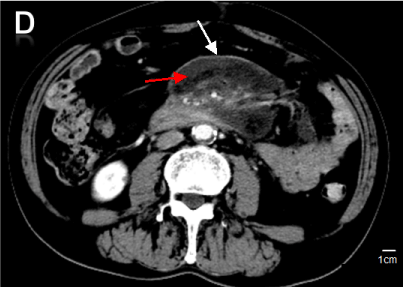

Superior Mesenteric Artery Syndrome Nhs. The syndrome may be precipitated by sudden weight loss secondary to other pathologies such as. Often acute occlusion of the SMA restricts blood flow to the midgut resulting in intestinal ischaemia. Superior Mesenteric Artery Syndrome Rani Sophia and Waseem Ahmad Bashir Yeovil Hospital NHS Foundation Trust Yeovil Somerset United Kingdom 1. Superior mesenteric artery syndrome SMAS Wilkie syndrome or cast syndrome is a rare condition that usually presents with symptoms of mid to upper gastrointestinal obstruction due to the compression of the duodenum between the abdominal aorta posteriorly and the superior mesenteric artery anteriorly.

Superior mesenteric artery syndrome SMAS is a digestive condition that occurs when the duodenum the first part of the small intestine is compressed between two arteries the aorta and the superior mesenteric artery.

A Systematic Review of Case Reports. Eating a liquid dietsoft foodchew things several yes lat on left side after food and during pain backup in fetal position during pain and rest. Rare syndrome characterized by symptoms resulting from vascular compressionobstruction of third part of duodenum in angle between aorta and superior mesenteric artery 1 clinical symptoms include nausea vomiting and post-prandial epigastric abdominal pain with or without associated weight loss and anorexia 1. Superior mesenteric artery syndrome SMAS Wilkie syndrome or cast syndrome is a rare condition that usually presents with symptoms of mid to upper gastrointestinal obstruction due to the compression of the duodenum between the abdominal aorta posteriorly and the superior mesenteric artery anteriorly. There are a number of cause of superior mesenteric artery occlusion including thrombosis embolism abdominal aortic aneurysm and aortic dissection. 1 Symptoms vary based on severity but can be severely debilitating.

Superior mesenteric artery syndrome is a rare digestive system disorder. Superior mesenteric artery syndrome is a gastro-vascular disorder in which the third and final portion of the duodenum is compressed between the abdominal aorta and the overlying superior mesenteric artery. It crosses over the first part of the small intestine called the duodenum. New Reply Follow New Topic. This rare potentially life-threatening syndrome is typically caused by an angle of 625 between the AA and the SMA in comparison to the normal range of 3856 due to.